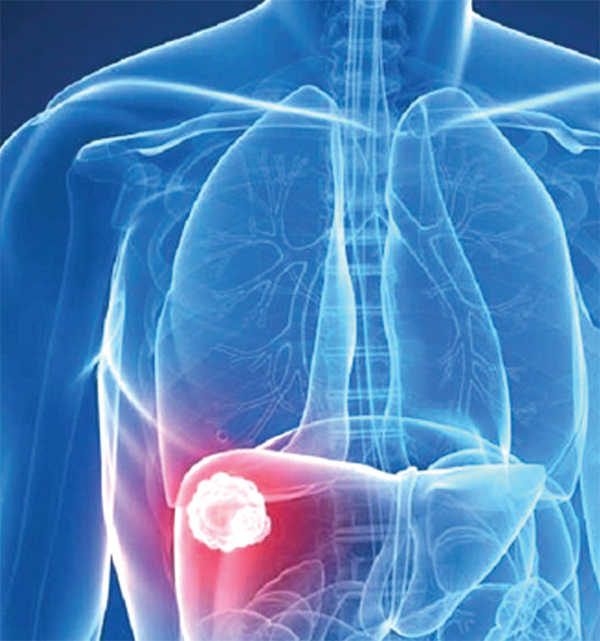

পাকস্থলীর ক্যান্সার খুবই জটিল একটি রোগ। এ ক্যান্সারে আক্রান্ত রোগীকে প্রচণ্ড কষ্ট পেতে হয়। এর চিকিৎসাও প্রায়ই তেমন ফলপ্রসূ হয় না। খুব সাধারণ কিছু উপসর্গ ও লক্ষণ থাকে পাকস্থলীর ক্যান্সারে, তাই রোগ ধরা পড়তে অনেক দেরি হয়ে যায়। তাই উপসর্গগুলো সম্পর্কে সবার ধারণা থাকা উচিত।

পাকস্থলীর ক্যান্সারে মৃত্যুঝুঁকি অনেক বেশি। তবে রোগটি প্রাথমিক পর্যায়ে নির্ণয় করা গেলে এবং অস্ত্রোপচারের মাধ্যমে ক্যান্সার আক্রান্ত স্থান কেটে ফেলে দিলে রোগী সুস্থ হতে পারেন।

চল্লিশোর্ধ্ব বয়সের পর যাঁদের হজমক্রিয়ার গোলযোগ হচ্ছে, তাদের এন্ডোস্কোপি করে প্রাথমিক অবস্থায় রোগ নির্ণয় করা জরুরি। আমাদের দেশে রোগীরা যখন চিকিৎসকের কাছে যান, তখন অধিকাংশ ক্ষেত্রেই ক্যান্সার পাকস্থলীর বাইরে ছড়িয়ে পড়ে। বিশেষ করে যকৃতে বা পেটের অন্যান্য অংশে ছড়িয়ে গেলে চিকিৎসা করা দুরূহ হয়ে পড়ে। এ জন্য সাধারণ সমস্যা দেখা দিলেও নিজে নিজে দিনের পর দিন গ্যাস্ট্রিকের ওষুধ খেয়ে সময় নষ্ট করা উচিত নয়। চিকিৎসকের পরামর্শ নেওয়া উচিত।